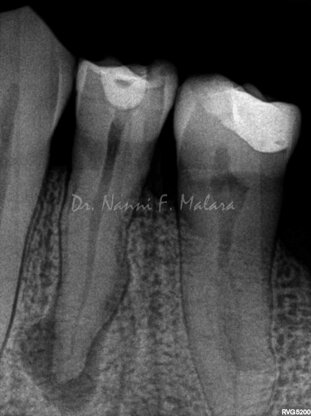

Premolare affetto da lesione periapicale (Alla radiografia si presenta come area scura intorno alla radice)

Terapia endodontica con sigillo tridimensionale del sistema canalare

Il controllo radiografico eseguito ad 8 mesi evidenzia l'avvenuta guarigione con il riassorbimento completo della lesione apicale.